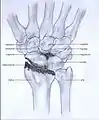

Post-traumatic osteoarthritis can be classified into four stages.[1][6] These stages are similar between SLAC and SNAC wrists. Each stage has a different treatment.

- Stage I: the osteoarthritis is only localized in the distal scaphoid and radial styloid.

Stage I